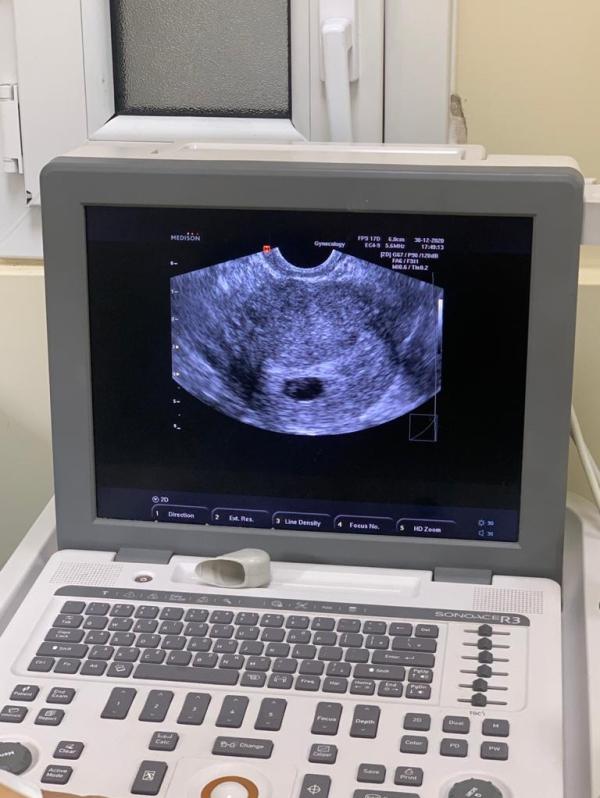

Девочки, врач отправила мне вчерашние фотки.. У кого были двойни, так ли было на 5-6 неделях? Меня смущает их размеры-один побольше, другой поменьше, третьего и не видно..

Она сказала похоже на тройняшек, но 2 точно есть

@katrin757 аа, поняла вас.. Просто там где побольше, сказала 6 недель и серцебиение уже заметно